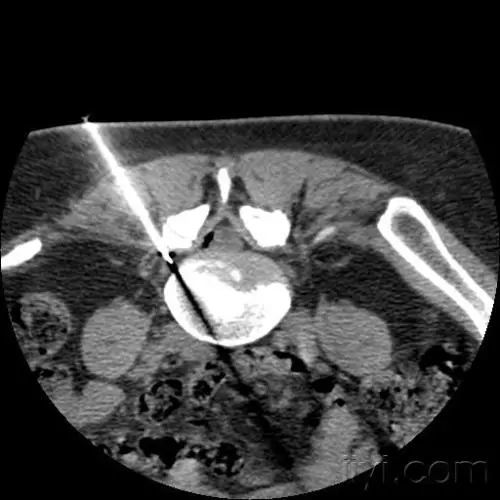

选择性神经根阻滞(特色技术)

对一部分患者效果明显 , 可明显减轻间歇性跛行症状 。

该手术是在可视化超声或者CT引导下将穿刺针经椎间孔穿刺到病变神经根处 , 松解粘连的神经根和硬脊膜囊 。 对缓解腰椎间盘突出症的神经根性疼痛有显著疗效 。 通过一次选择性神经根松解阻滞术 , 既可缓解患者腰腿痛症状 , 又可定位引起患者疼痛症状的神经根节段 , 明确诊断 , 为后期行开放性手术精准定位了责任节段 , 可谓“一石二鸟” 。

文章插图